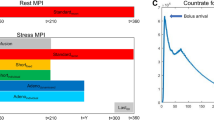

Reproduction of Artifact on Intentionally Misaligned Studies

Analysis of the data for the six normal studies that were intentionally misaligned at stress demonstrated that with each degree of intentional shift (5 mm, 7.5 mm, etc) there was a significant increased risk of misalignment (Table 7) and that there was a significant correlation (Fig. 1) of the size of the artifactual defect (as compared to a normal file quantitative algorithm) with misalignment. Yet, this effect was variable. While misalignment of 10 cc or greater always resulted in some artifactual defect, misalignment of less than this amount in some cases resulted in no significant artifactual defect or relatively large defects. Artifactual defects of 5% or greater occurred with apparent misalignment of less than 1 cc in some instances.

Scatter plot correlating the size of the artifactual defect (% left ventricular mass as defined by the quantitative algorithm) to misalignment/misregistration of the emission/transmission images in six shifted normal studies. On average, the artifactual defect increases by 1.14% per cubic centimeter increase in misalignment. The rate of increase is statistically significantly (p < 0.0001). Note though, that no defect may occur with a misalignment of up to 9.2 cc, and defects 5% or greater may occur with misalignment of less than 1 cc in an individual patient.